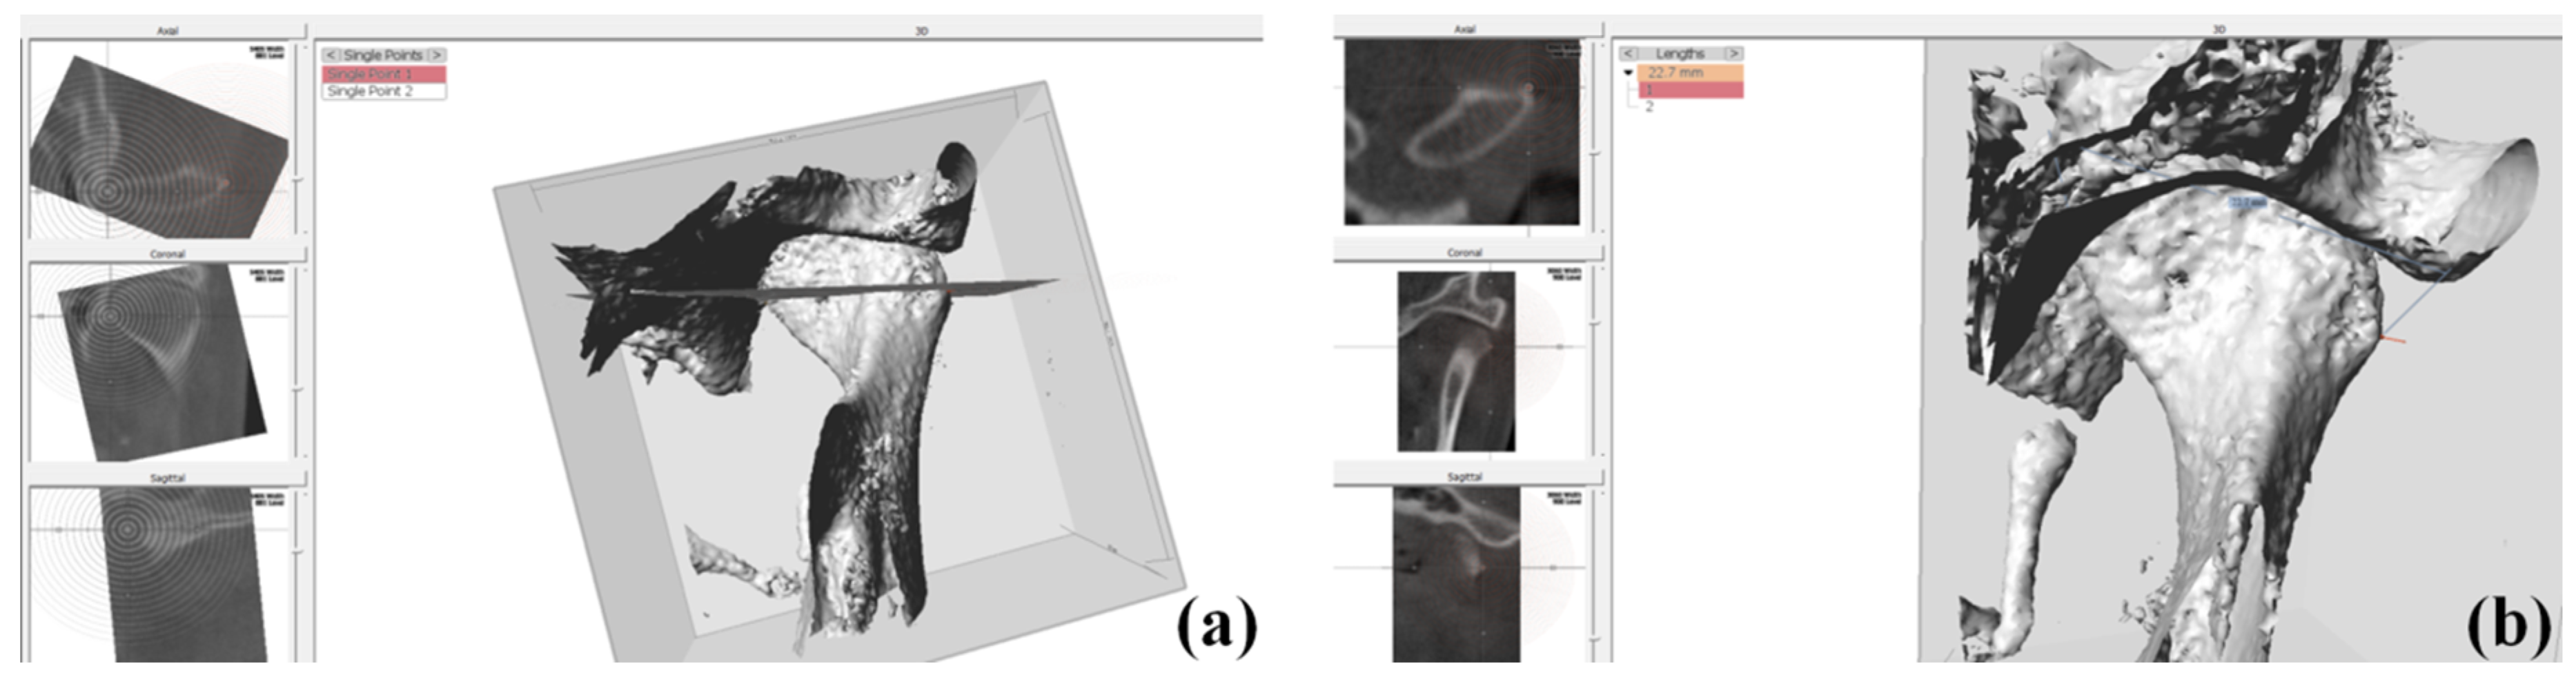

2.3. Condylar Volume Rendering